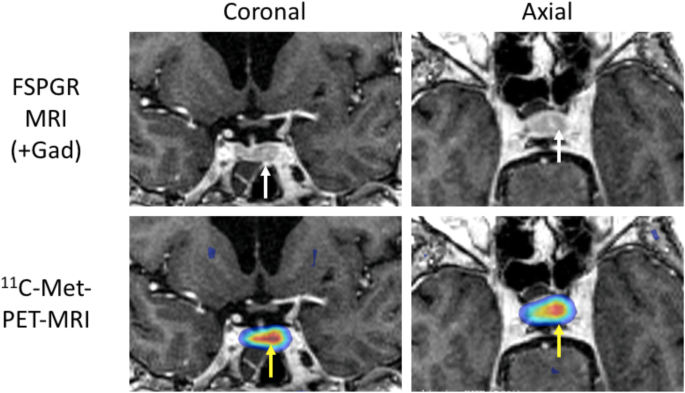

A pituitary MRI scan showed asymmetric enlargement of the gland, raising the possibility of a left-sided pituitary microadenoma (Fig. 2). An 11C-methionine PET/CT scan was performed and coregistered with a volumetric [fast spoiled gradient recall (FSPGR) MRI scan (Met-PET-MRICR)]. This demonstrated focal increased tracer uptake at the site of the suspected microadenoma (Figs. 3 and 4). Her biochemical and radiological findings were therefore consistent with the diagnosis of a TSH-secreting pituitary adenoma. The slightly raised IGF-1 and borderline suppression of GH on OGTT also raised the possibility of GH co-secretion. The patient was tried on a somatostatin analogue (SSA) first then a dopamine agonist but did not tolerate either (due to gastrointestinal side-effects). She declined pituitary surgery. She is currently managed with a beta-adrenergic blocker and is clinically euthyroid.

In recent years, functional pituitary imaging has been proposed as a useful tool for identifying the site(s) of a pituitary adenoma in patients with inconclusive MRI findings [26]. 11Carbon-methionine is an amino acid based PET tracer which, unlike the glucose-based tracer 18F-fluorodeoxyglucose, is preferentially taken up by normal pituitary tissue [27] with relatively low uptake by background brain tissue. Coregistration of 11C-Methionine PET/CT and volumetric (e.g FSPGR) MRI may be superior to MRI alone in localizing some pituitary microadenomas [16, 28, 29]

Inferior petrosal sinus sampling (IPSS) is often considered the gold standard investigation for the diagnosis of functional pituitary tumours. This is an invasive test that requires significant technical expertise. While more data is needed on the utility of Met-PET-MRICR there is some evidence to suggest it is a highly sensitive non-invasive test that could be considered as an alternative to IPSS [30]. In our case, although MRI raised suspicion of a left-side abnormality, no definite adenoma was seen. However, Met-PET-MRICR confirmed focal tracer uptake corresponding to this site.